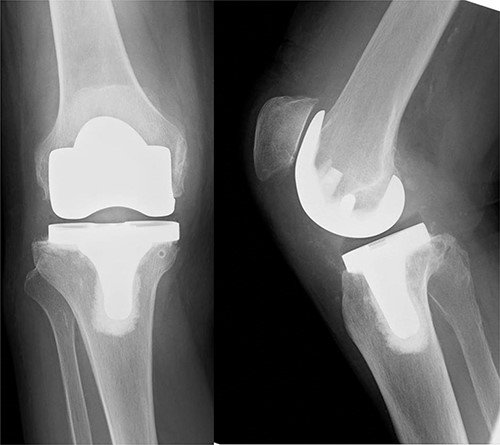

An 82-year-old woman underwent bilateral TKA for Grade IV knee osteoarthritis. The surgery was performed through a midline gentle curved incision and a trivector approach. Cemented medial pivot implants (Medacta® GMK-Sphere, Medacta International: Castel S. Pietro, Switzerland) were placed. No resurfacing was performed because of the anterior tilt of the patella during surgery. Recovery was uneventful, and the patient was able to walk comfortably without support 3 weeks post-operatively. After 1 week, she felt pain in the right knee joint without any specific triggers. Her gait was stiff, and she needed support to walk. Range of motion testing showed knee extension of −35° and knee flexion of 80°. There was no warmth or redness in the right knee. Tenderness at the tibial tuberosity was mild, and radiographic examination showed patellar alta (Fig. 1).

After hemostasis, the wound closed in layers. The patient had a cylinder cast for 4 weeks and was allowed full weight-bearing. At 4 weeks post-operatively, the knee was immobilized, and dynamic quadriceps exercises were initiated. The patient regained pain-free motion from 0° to 100° without extension lag. She could walk without a cane 3 months post-operatively. X-rays also showed no patellar alta (Fig. 5).

X-ray, 3 months post-operatively, did not show any patellar alta.